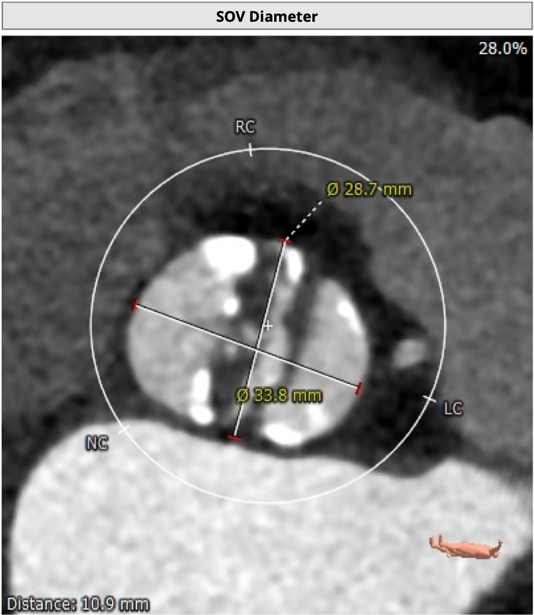

主动脉根部评估

CT 数据显示该患者为二叶式主动脉瓣

LVOT 周长74.6mm,周长径23.8mm;

SOV 28.7mm*33.8mm;

STJ 短径29.9mm,长径31.6mm;

瓣叶增厚,重度钙化,1075HU:1762mm³;

瓣环水平夹角48度。

左冠开口高度14.2mm,右冠开口高度18.4mm,左右冠脉高度可。